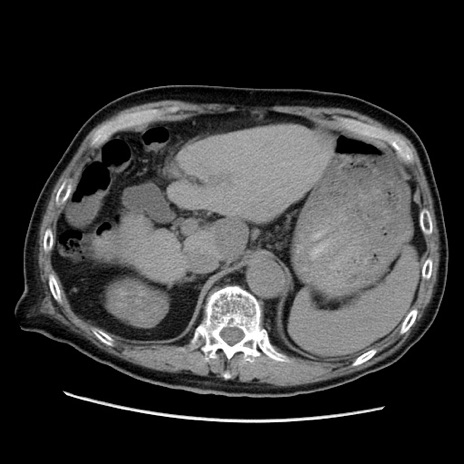

症例21(横断像)

【症例】70歳代男性

【主訴】腹痛

【現病歴】肝硬変・肝細胞癌にてかかりつけの方。約9時間前に食後より腹痛出現。症状が徐々に増悪し、嘔吐出現したため来院。

【既往歴】肝硬変、肝細胞癌(RFA、TACE後)

【身体所見】意識清明、表情苦悶様、BT 36℃、BP 129/78mmHg、P 88bpm、SpO2 97%(RA)、右上腹部から心窩部にかけて圧痛あり、反跳痛なし、筋性防御あり。

【データ】WBC 5800、CRP 0.16